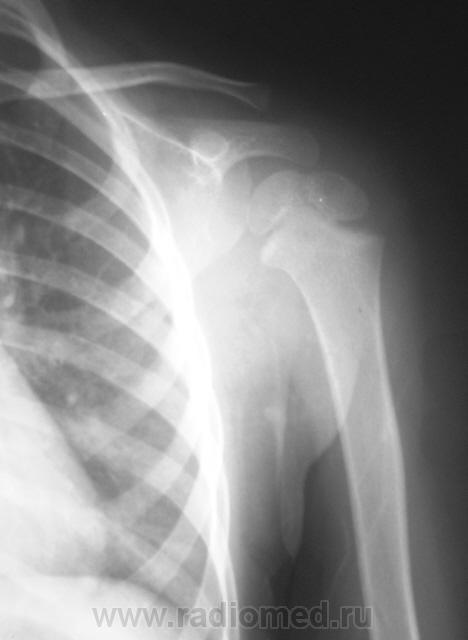

Пол пациента: Мужской пол Тип патологии: Травма Область исследования: Скелетно-мышечная система Методы исследования: Rg Ребенок доставлен по «ургенту». Травма. Направлен на рентгенографию левого плечевого сустава. https://radiomed.ru/sites/default/files/styles/case_slider_image/public/user/12/2.p1190014a.jpg?itok=1gdJVd7R https://radiomed.ru/sites/default/files/styles/case_slider_image/public/user/12/3.p1190015.jpg?itok=J2sCFP2r https://radiomed.ru/sites/default/files/styles/case_slider_image/public/user/12/4.p1190015a.jpg?itok=J9XWCaEU ID:11399 Ср, 19/01/2011 - 17:41 #1 Катенёв Валенти... Не на сайте Был на сайте: 7 лет 2 недели назад Зарегистрирован: 22.03.2008 - 22:15 Публикации: 54876 Для сравнения, дежурный хирург, попросил сделать правый плечевой сустав.Приложения: Ср, 19/01/2011 - 18:50 #2 Vega Не на сайте Был на сайте: 3 месяцев 1 неделя назад Зарегистрирован: 22.01.2009 - 19:16 Публикации: 1087 Перелом левой ключицы Ср, 19/01/2011 - 19:22 #3 Ola-la Не на сайте Был на сайте: 10 месяцев 6 дней назад Зарегистрирован: 06.12.2008 - 09:33 Публикации: 1786 Может быть, если есть клиника, но немного сомнительно. А почему опять нет второй проекции? https://www.instagram.com/pediatricradiology/ Ср, 19/01/2011 - 20:11 #4 Катенёв Валенти... Не на сайте Был на сайте: 7 лет 2 недели назад Зарегистрирован: 22.03.2008 - 22:15 Публикации: 54876 Ola-la wrote: Может быть, если есть клиника, но немного сомнительно. А почему опять нет второй проекции? Ургент! Как дежурный врач требует, так лаборант и делает. Ср, 19/01/2011 - 21:25 #5 Ola-la Не на сайте Был на сайте: 10 месяцев 6 дней назад Зарегистрирован: 06.12.2008 - 09:33 Публикации: 1786 А у нас дежурные требуют всегда в двух проекциях. https://www.instagram.com/pediatricradiology/ Ср, 19/01/2011 - 21:54 #6 Катенёв Валенти... Не на сайте Был на сайте: 7 лет 2 недели назад Зарегистрирован: 22.03.2008 - 22:15 Публикации: 54876 Ola-la wrote: А у нас дежурные требуют всегда в двух проекциях. Сравнили! У Вас, кто дежурит? А, у нас кто? Ваши, что-то хоть сделают, а наши в основном наблюдают...с определенного расстояния.

Для сравнения, дежурный хирург, попросил сделать правый плечевой сустав.

Перелом левой ключицы

Может быть, если есть клиника, но немного сомнительно. А почему опять нет второй проекции?